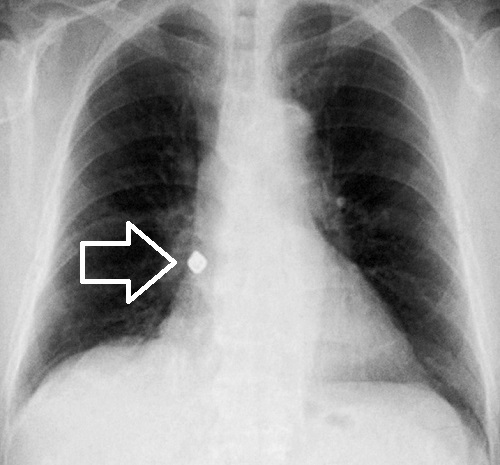

特に高齢者などで、食べている最中に差し歯、義歯、歯のかぶせ(歯冠)を知らずに飲み込んでしまい(誤嚥)、むせたり、咳き込むことがあります。人工歯が外れたのに気付かず、喉(のど)に引っ掛かる感じがするので、甲状腺の病気と勘違いする人もいます。しかし、人工歯は気管支まで落ちて、気管支異物になっています。

子供などでは、未発達な歯が体育の授業中に折れたり、抜けたりして気管支異物にる可能性があります。小学生の歯の外傷は水泳、体操、鉄棒の最中に起こりやすい。

気道異物は、

- 乳幼児と高齢者に多い

- 分岐角の小さい右側に多い

- Holzknecht sign ;縦隔が吸気時に患側へ、呼気時に健側へ偏位